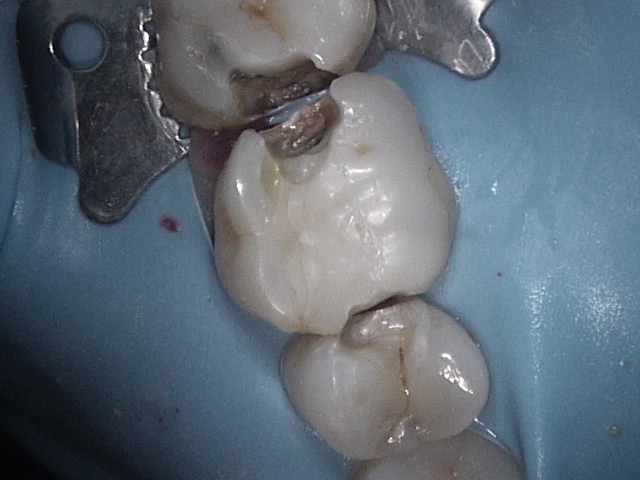

At Ottawa Dental Care, we understand that restoring the health of your teeth doesn’t have to compromise your smile’s natural beauty. White fillings, also known as composite fillings, are a discreet and durable solution for repairing cavities, chips, or cracks in your teeth. Designed to blend seamlessly with the natural color of your teeth, white fillings are a popular choice for patients looking to maintain a flawless smile.

White fillings are made of a tooth-colored composite resin that bonds directly to your tooth. Unlike silver amalgam fillings, they blend naturally with your teeth, making them virtually invisible.

Fillings are used to repair teeth damaged by decay, cracks, or wear. When a cavity forms, it creates a hole in the tooth that can lead to pain, infection, or further damage if left untreated. A filling restores the tooth’s structure and function, preventing the problem from worsening.